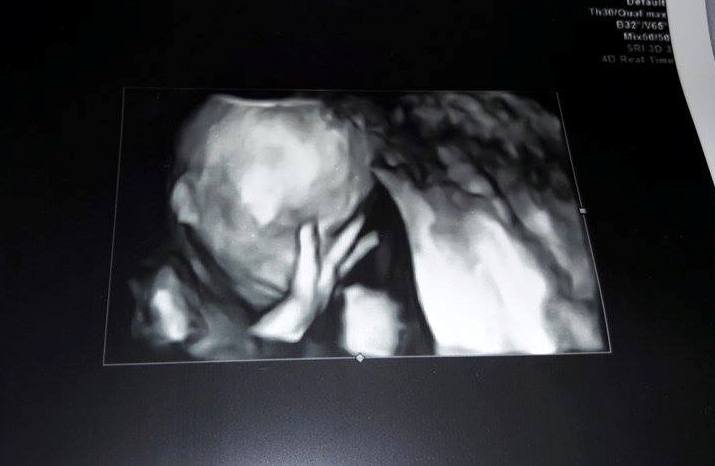

Ai împlinit 18 săptămâni și 2 zile. Ți-am văzut inima cum bate, astăzi te-am văzut mare și frumos. M-am panicat că

aveai cordonul ombilical în jurul gâtului și am întrebat medicul de 2 ori dacă

ești bine. Azi ți-am văzut mânuțele și piciorușele. Ți-am văzut mutrița aia

mică și am simțit o dragoste care nu se poate descrie în cuvinte. Am simțit

nevoia să-ți mângâi fruntea. Am început să plâng de nepuțintă și frustrare, de

dor de bunicul tău, iar tu atunci ți-ai dus mâna la față, puiule. Ți-ai dus

mână la față și apoi la ochi. Azi am conștientizat că toate suferința mea ai